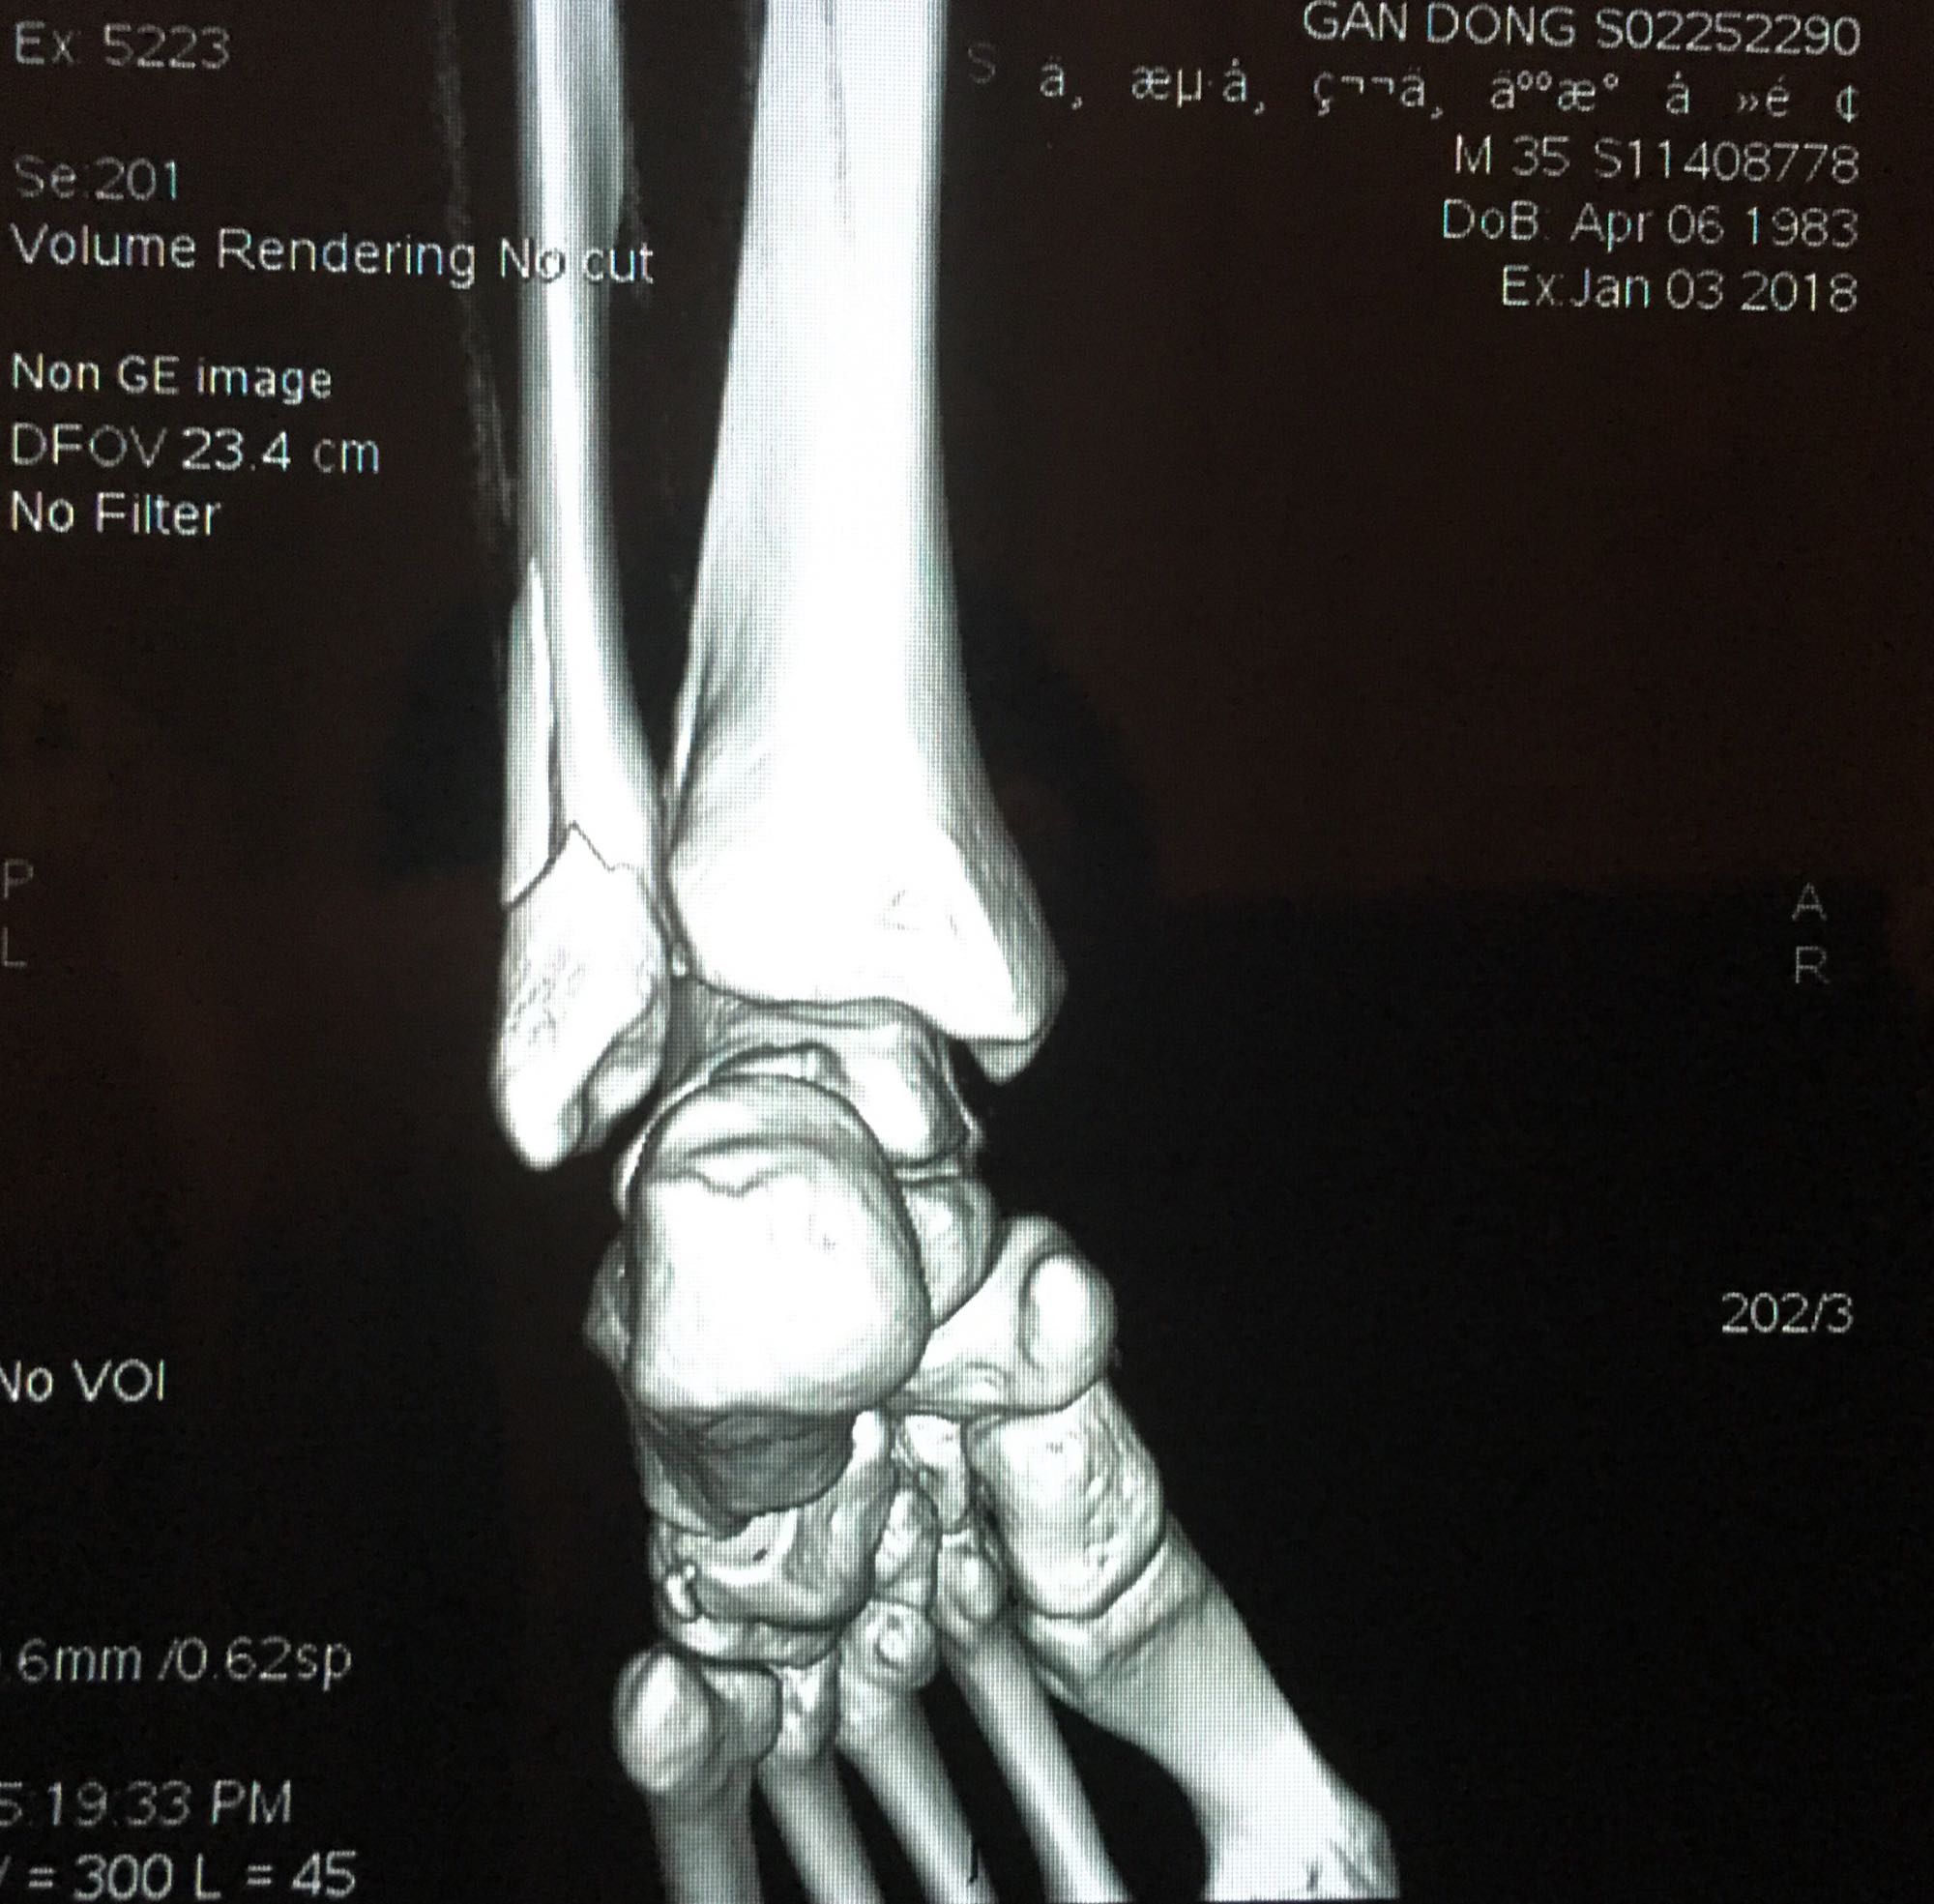

腓骨靠近踝关节处骨折,已经第七天了,西医建议手术,中医说不手

三踝骨折吧

腓骨靠近踝关节处骨折,已经第七天了,西医建议手术,中医说不手术固定好也可,迷茫中……

这个不是近关节骨折,这个是关节内骨折,关节腔肯定伤到了。手术并正确康复训练的话后遗症小,保守治疗后期康复很痛苦,同时高风险有后遗症

回复 gandong1181 :就是骨折恢复时会有增生物在关节内,造成走路疼痛或者关节僵硬,进一步破坏关节软骨,严重的会慢慢的破坏距骨直至距骨坏死,最终瘫痪或者做关节融合术。